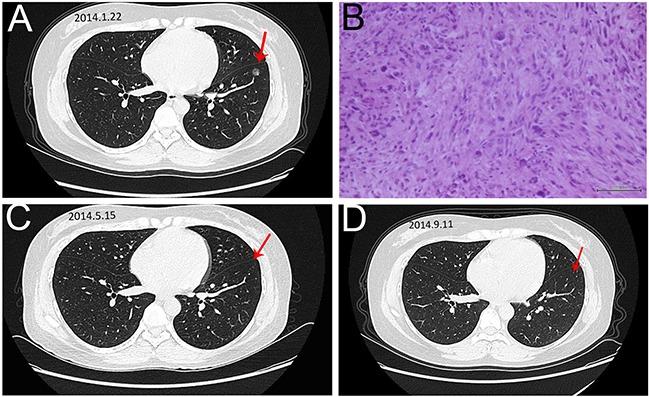

Recombined humanized endostatin (Endostar) combined with chemotherapy for advanced bone and soft tissue sarcomas in stage IV.

This retrospective case-series study evaluated efficacy and safety of Endostar combined with chemotherapy in the treatment of advanced bone and soft tissue sarcomas in stage IV.

Endostar combined with chemotherapy had significantly increased PFS. In the combined group and control groups, the median PFS (8.6 months versus 4.4 months) and the CBR (47.8% versus 16.7%) showed significant difference (P = 0.032), while the median overall survival (11.7 months versus 10.6 months, P = 0.658) and the ORR (17.4% versus 8.3%, P = 0.167) showed no significant difference. The common grade 3-4 side effects for both groups were myelosuppression and transient elevation of transaminases.

Endostar combined with chemotherapy had significant activity to increase the PFS and improve CBR in patients with advanced sarcomas, with tolerable side effects.